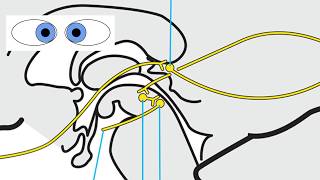

RS Supranuclear Ocular Motor Pathways Part 2 - Vertical Saccades

RS Supranuclear Ocular Motor Pathways Part 2 - Vertical Saccades RS Supranuclear Ocular Motor Pathways Part 1 - Horizontal Saccades

RS Supranuclear Ocular Motor Pathways Part 3 - Pursuit Vertical eye movement pathway | Neuroaholics

RS Supranuclear Ocular Motor Pathways Part 2 - Vertical Saccades

RS Supranuclear Ocular Motor Pathways Part 2 - Vertical Saccades RS Supranuclear Ocular Motor Pathways Part 1 - Horizontal Saccades

RS Supranuclear Ocular Motor Pathways Part 3 - Pursuit Vertical eye movement pathway | Neuroaholics